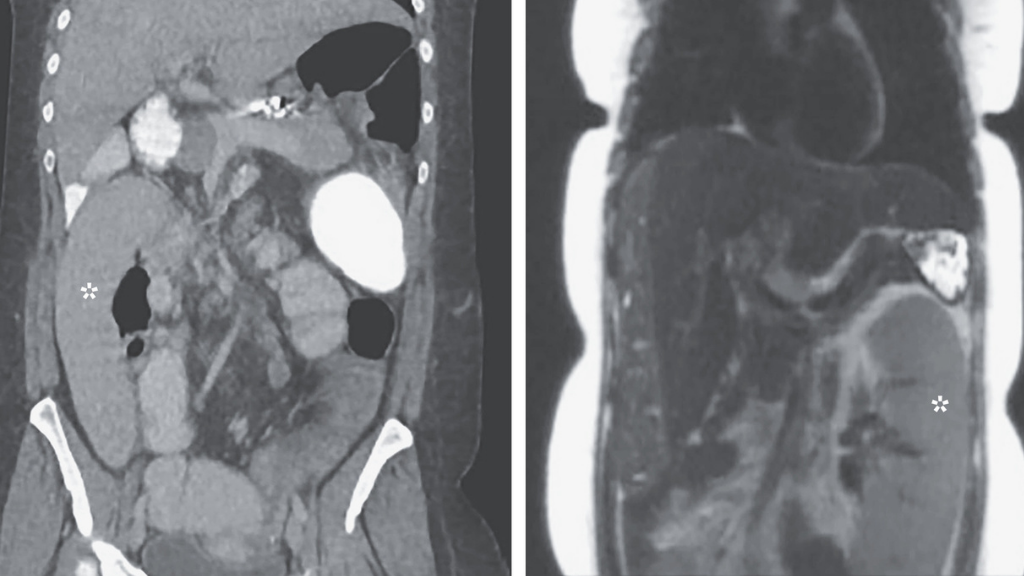

Even if your mind wanders, you can typically count on your physical organs to remain in the same place inside your body. However, as a woman in Michigan discovered when her spleen migrated a full foot within her body in 48 hours, this isn't always the case. The woman had "wandering spleen," an uncommon disorder in which the ligaments that maintain the spleen in its normal location become weaker, allowing the organ to travel inside the body. According to a case report published Nov. 19 in The New England Journal of Medicine, CT images of the woman's abdomen done just two days apart revealed that her spleen had migrated from the upper left quadrant to the lower right quadrant. According to the authors, that's around a one-foot (0.3-meter) distance. The woman had a liver problem that caused her spleen to enlarge, causing the ligaments that surrounded her spleen to stretch. The excision of the spleen is the most common treatment for wandering spleen. However, in this situation, the woman was hoping for a liver transplant, and removing her spleen separately could cause complications that would prevent her from receiving a new liver. As a result, doctors opted to hold off, planning to remove her spleen at the same time as her liver transplant.